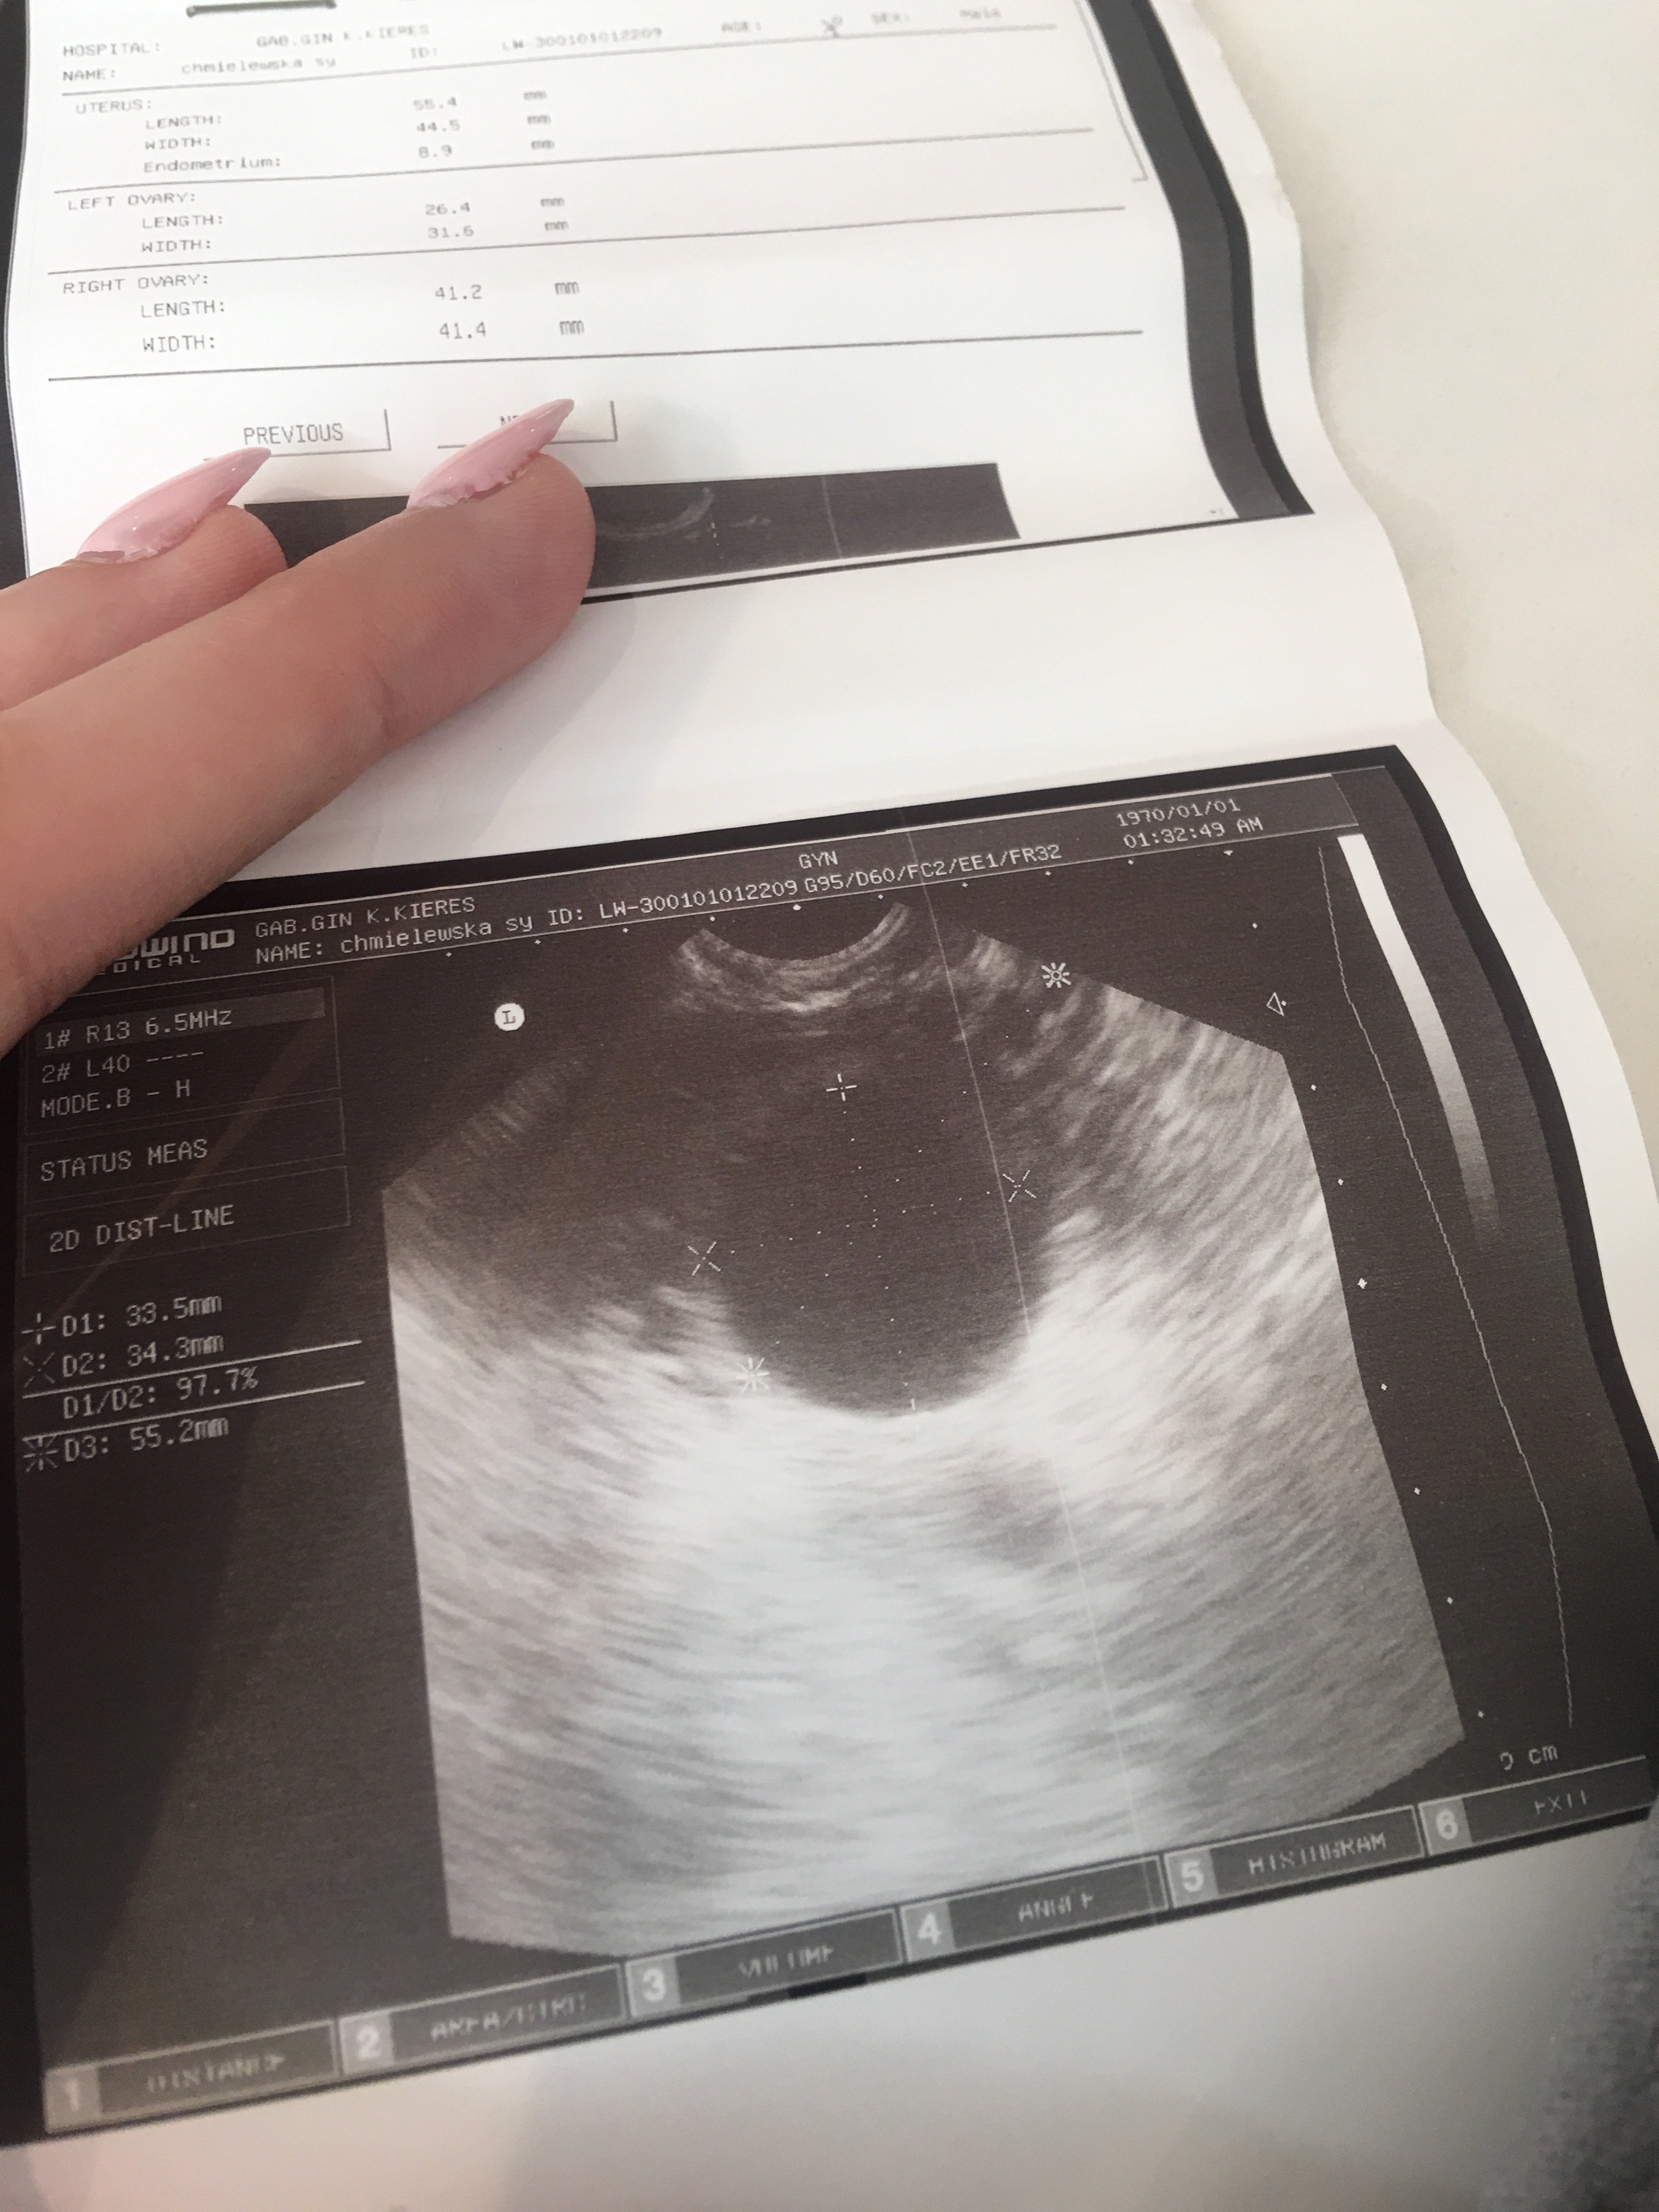

Witam staramy się o dzidziusia. W dniu spodziewanej miesiączki gdy nie przyszła zrobiłam test ciążowy wyszła 2 blada kreska po dwóch dniach to samo. Ucieszona poszłam do lekarza ponieważ tez od 3 dni miałam jakieś swędzenie miejsc intymnych. Lekarka zasmuciła mnie ze ciąży narazie nie widać za to mam torbiel 33,5 mm na prawym jajniku. Zaleciła branie dalej kwasu foliowego globulki dopochwowe na ta infekcje ponieważ mówi ze jestem w środku cała napuchnięta i zaczerwieniona. Kazała iść za kilka dni na betę i za tydzień przyjść na kontrole. Powiem wam ze lekko się załamałam ze nie wyszło. Pozatym dokucza mi od 4 dni dyskomfort podbrzusza i lekki ból pleców. Jestem rozdrażniona i zmęczona. Jak myslicie jest szansa na ciąże czy to torbiel zafalszowal wyniki testu.

Witam staramy się o dzidziusia. W dniu spodziewanej miesiączki gdy nie przyszła zrobiłam test ciążowy wyszła 2 blada kreska po dwóch dniach to samo. Ucieszona poszłam do lekarza ponieważ tez od 3 dni miałam jakieś swędzenie miejsc intymnych. Lekarka zasmuciła mnie ze ciąży narazie nie widać za to mam torbiel 33,5 mm na prawym jajniku. Zaleciła branie dalej kwasu foliowego globulki dopochwowe na ta infekcje ponieważ mówi ze jestem w środku cała napuchnięta i zaczerwieniona. Kazała iść za kilka dni na betę i za tydzień przyjść na kontrole. Powiem wam ze lekko się załamałam ze nie wyszło. Pozatym dokucza mi od 4 dni dyskomfort podbrzusza i lekki ból pleców. Jestem rozdrażniona i zmęczona. Jak myslicie jest szansa na ciąże czy to torbiel zafalszowal wyniki testu. Zobacz załącznik 1135140